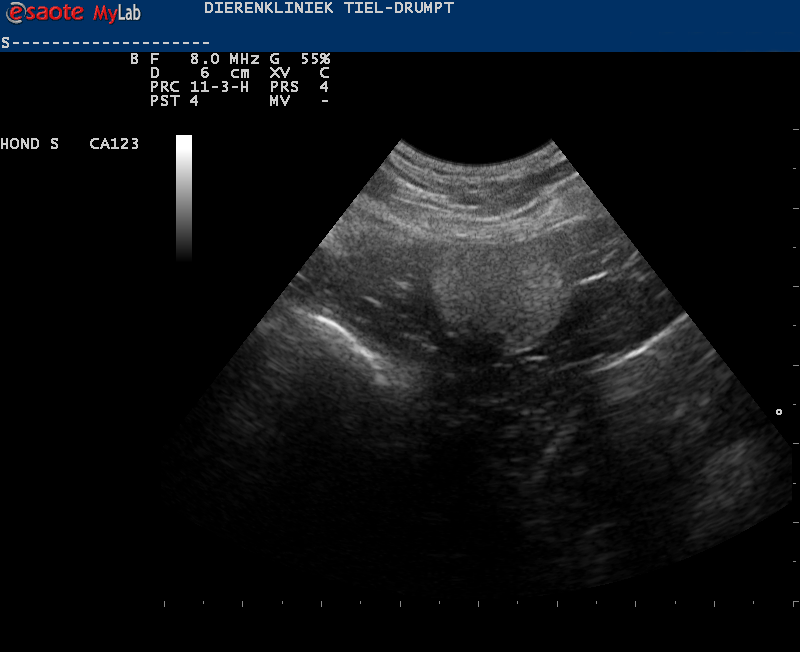

Denk hierbij bijvoorbeeld aan het verwijderen van een binnenbal die in de buik ligt (cryptorche testikel), waarbij er laparoscopisch geassisteerd wordt. Door middel van een echo is er eerst gekeken waar de testikel ligt.